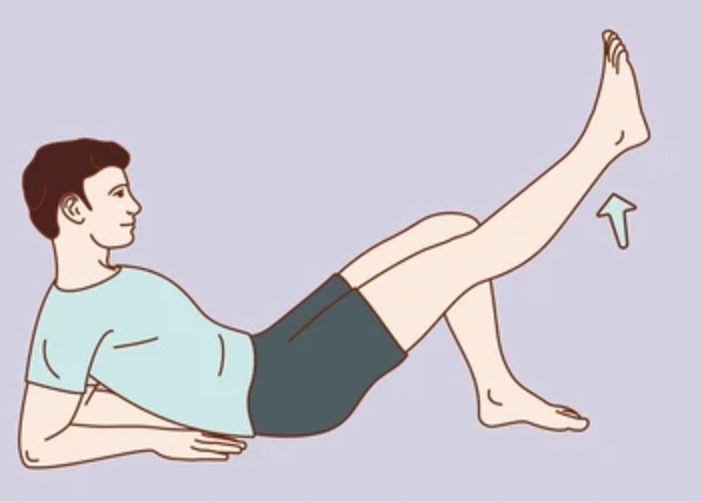

추운 겨울철에도 실내에서 안전하게 할 수 있는 관절 운동을 소개합니다:

- 앉았다 일어나기 운동 (하루 10회씩 3세트)

- 다리 들어올리기 (각 다리 15초씩 유지)

- 무릎 굽혔다 펴기 (20회씩 3세트)